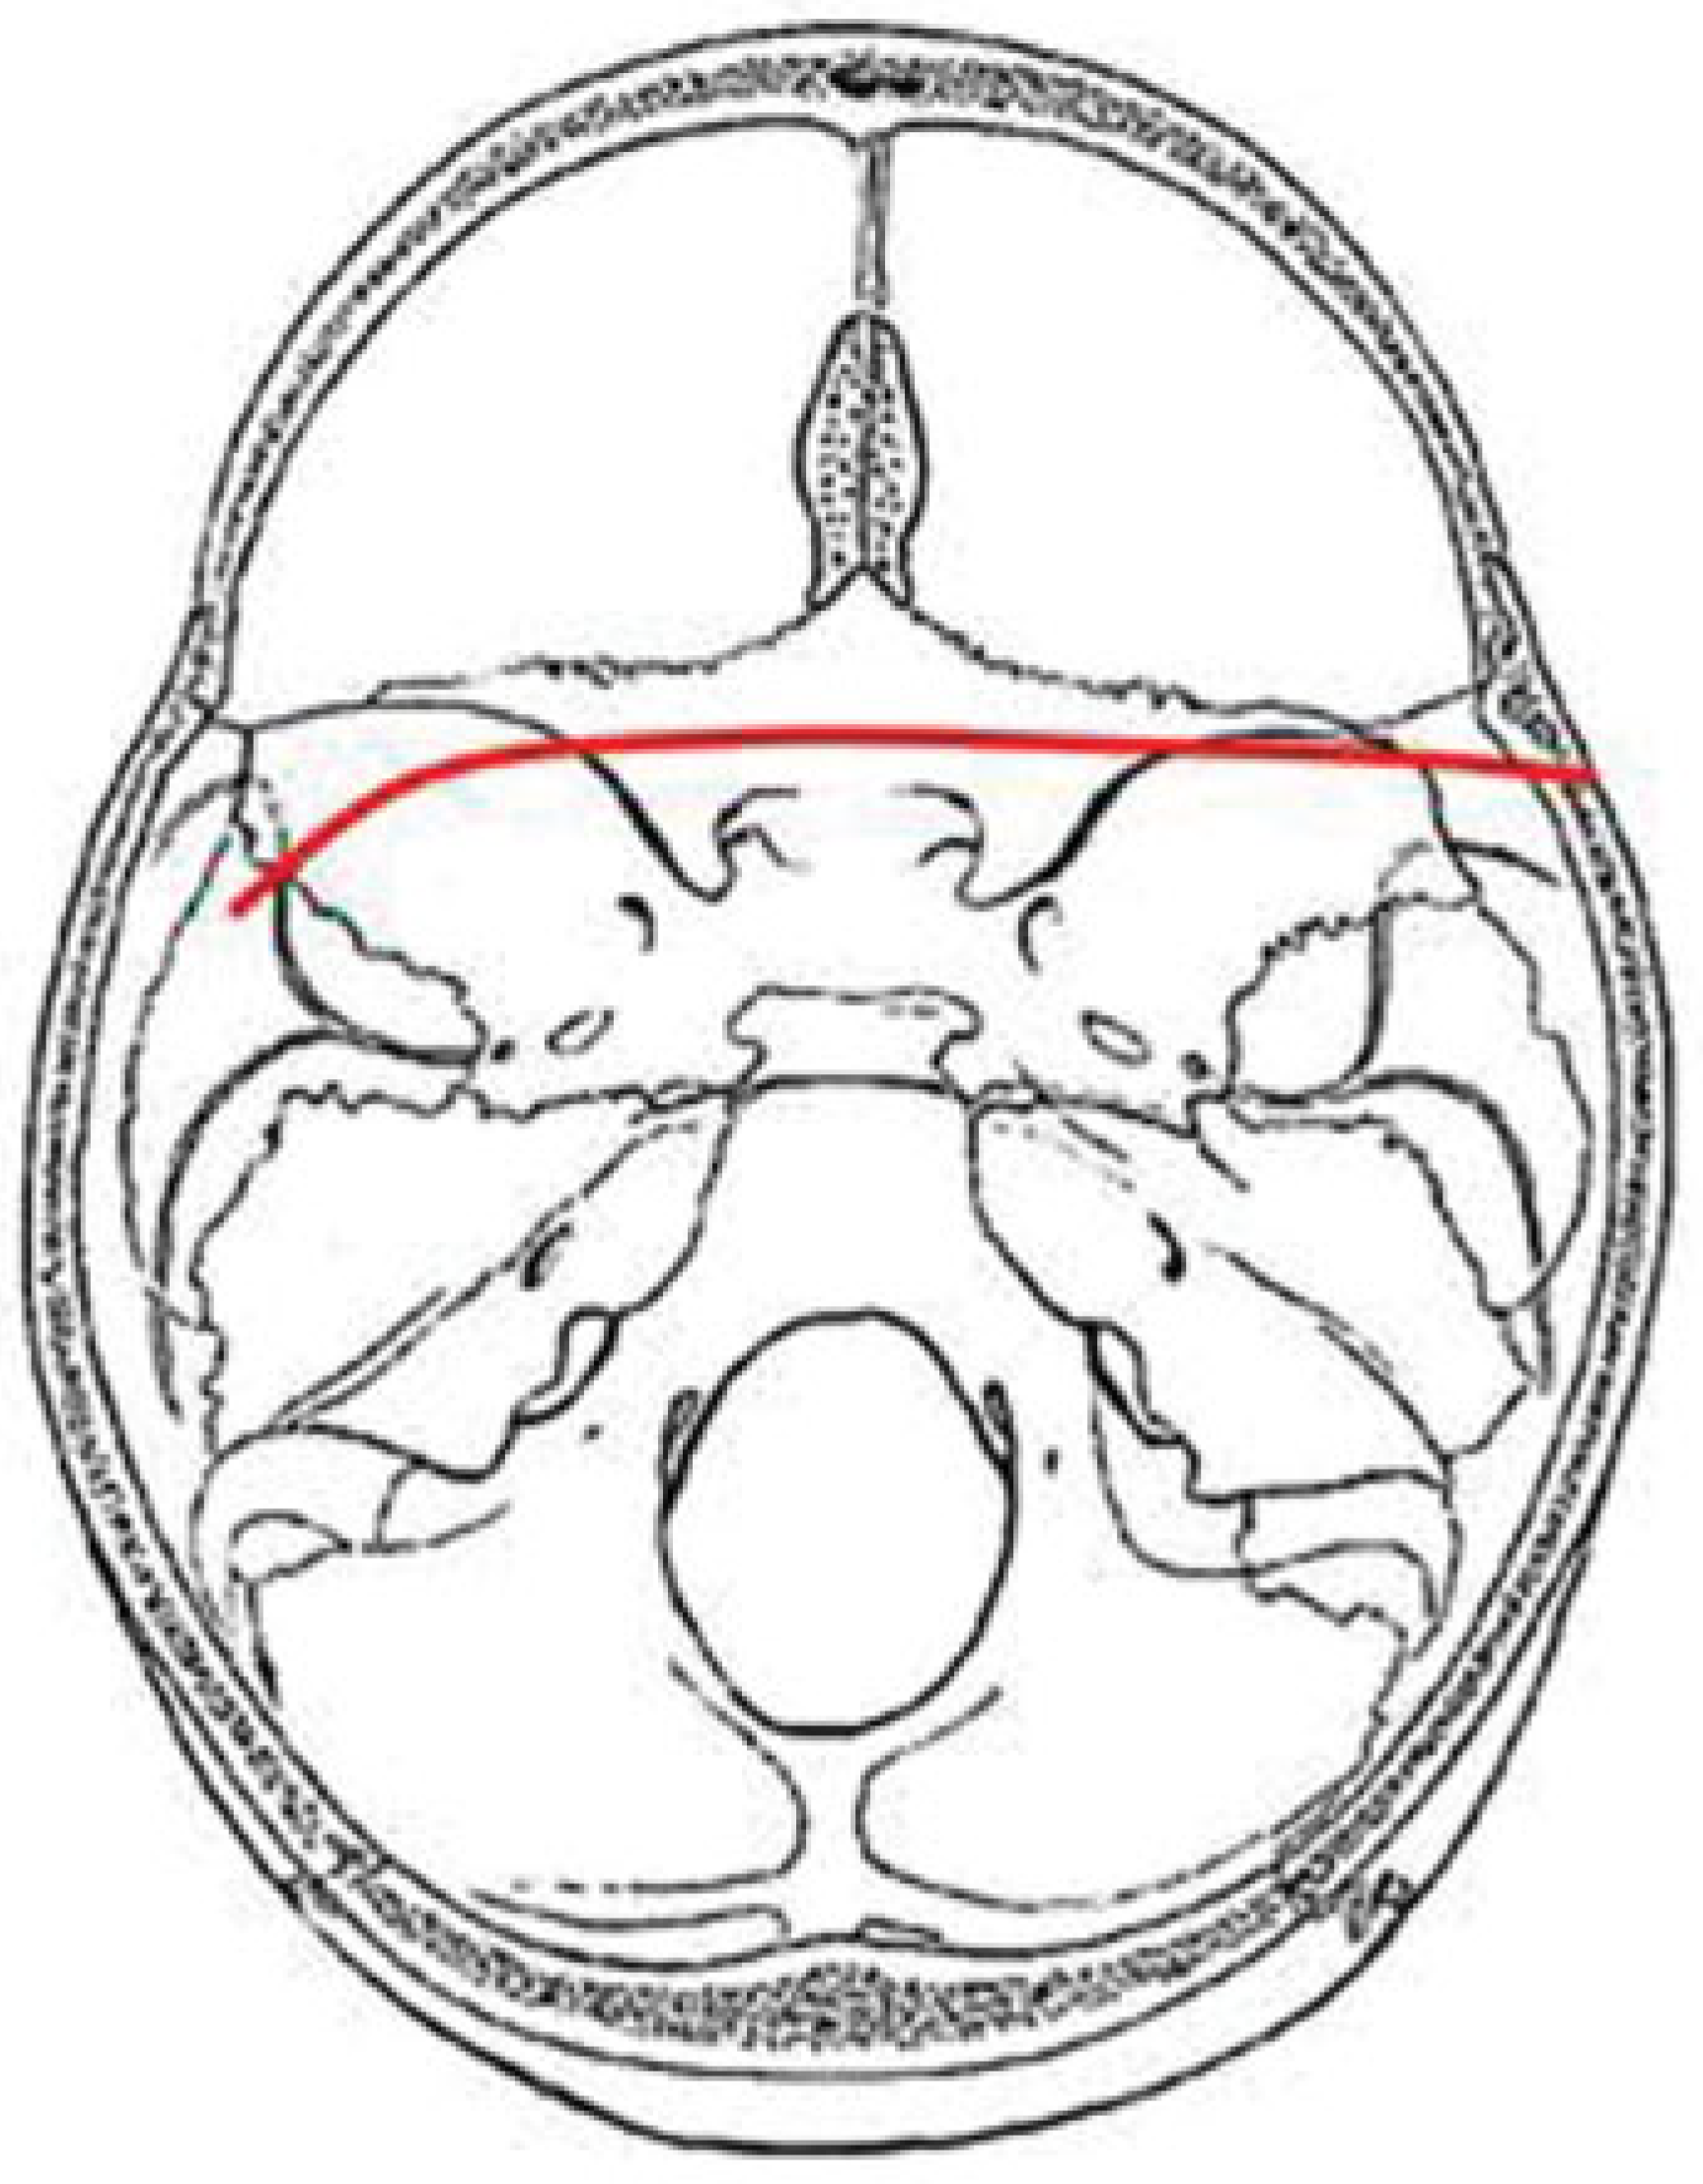

PT Pattern

PT fractures usually have a characteristic inverted U shape, with fractures extending from one temporal bone, across the middle cranial fossa to the posterior sphenoid body and clivus, then to opposite middle cranial fossa, and then on to the opposite temporal bone. The hallmark of this fracture pattern is the demonstration of a transverse fracture through the posterior sphenoid sinus or clivus. The exact location of this fracture occurs most frequently at the posterior wall of the sphenoid sinus but sometimes a few millimeters anterior or posterior to this location. The fracture usually results from lateral impact to the skull and enters the skull base in the tympanic portion of the temporal bone anterior to the external auditory canal and inferoposterior to the mandibular fossa of the temporal bone (Figure 7).

Figure 7. Composite drawing of the posterior transverse pattern (left impact).